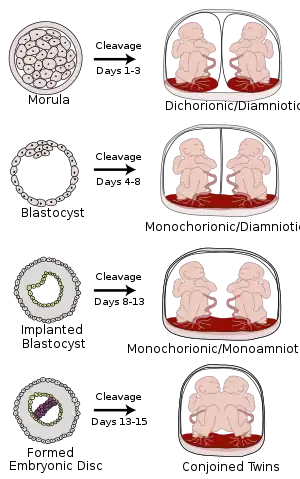

Monoamniotic twins are identical or semi-identical twins that share the same amniotic sac within their mother's uterus.[1] Monoamniotic twins are always monochorionic and are usually termed Monoamniotic-Monochorionic ("MoMo" or "Mono Mono") twins.[1][2] They share the placenta, but have two separate umbilical cords. Monoamniotic twins develop when an embryo does not split until after formation of the amniotic sac,[1] at about 9–13 days after fertilization.[3] Monoamniotic triplets or other monoamniotic multiples[4] are possible, but extremely rare.[1] Other obscure possibilities include multiples sets where monoamniotic twins are part of a larger gestation such as triplets, quadruplets, or more.